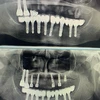

Implant tedavisi

Periimplantitis

Peri-İmplant Mukozitis